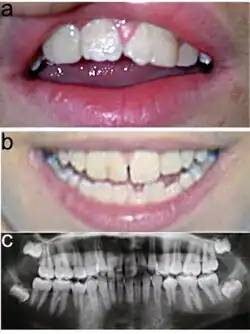

Typisch für das KBG-Syndrom sind faziale Dysmorphien (Gesichtsdysmorphien) und große obere mittlere Schneidezähne. Dazu kommen Anomalien des Skeletts, vor allem costovertebral, das heißt an den Rippenwirbeln, und eine verzögerte körperliche Entwicklung. Letztere führt zu Minderwuchs. Bei der Mehrzahl der Patienten finden sich außerdem EEG-Anomalien (mit oder ohne Krampfanfällen) und ein abnormer Haaransatz. Deutlich seltener sind kutane Syndaktylie, kurzer Hals mit Pterygium, Kryptorchismus („Bauchhoden“), Schwerhörigkeit, Schielen, Gaumendefekt und angeborene Herzfehler.[2]

Die Diagnosestellung erfolgt im Wesentlichen aufgrund der Symptome, da noch kein Gentest für das KBG-Syndrom verfügbar ist. Dabei orientiert man sich an vier wesentlichen Merkmalen des KBG-Syndroms: faziale Dysmorphie, Makrodentie der oberen mittleren Schneidezähne, skelettale Anomalien (vor allem costovertebral) und verzögerte Entwicklung. Im Alter von sieben bis acht Jahren lässt sich mit der Ausbildung der vorderen Schneidezähne über die Makrodentie die Diagnose sicherer erstellen.[2]